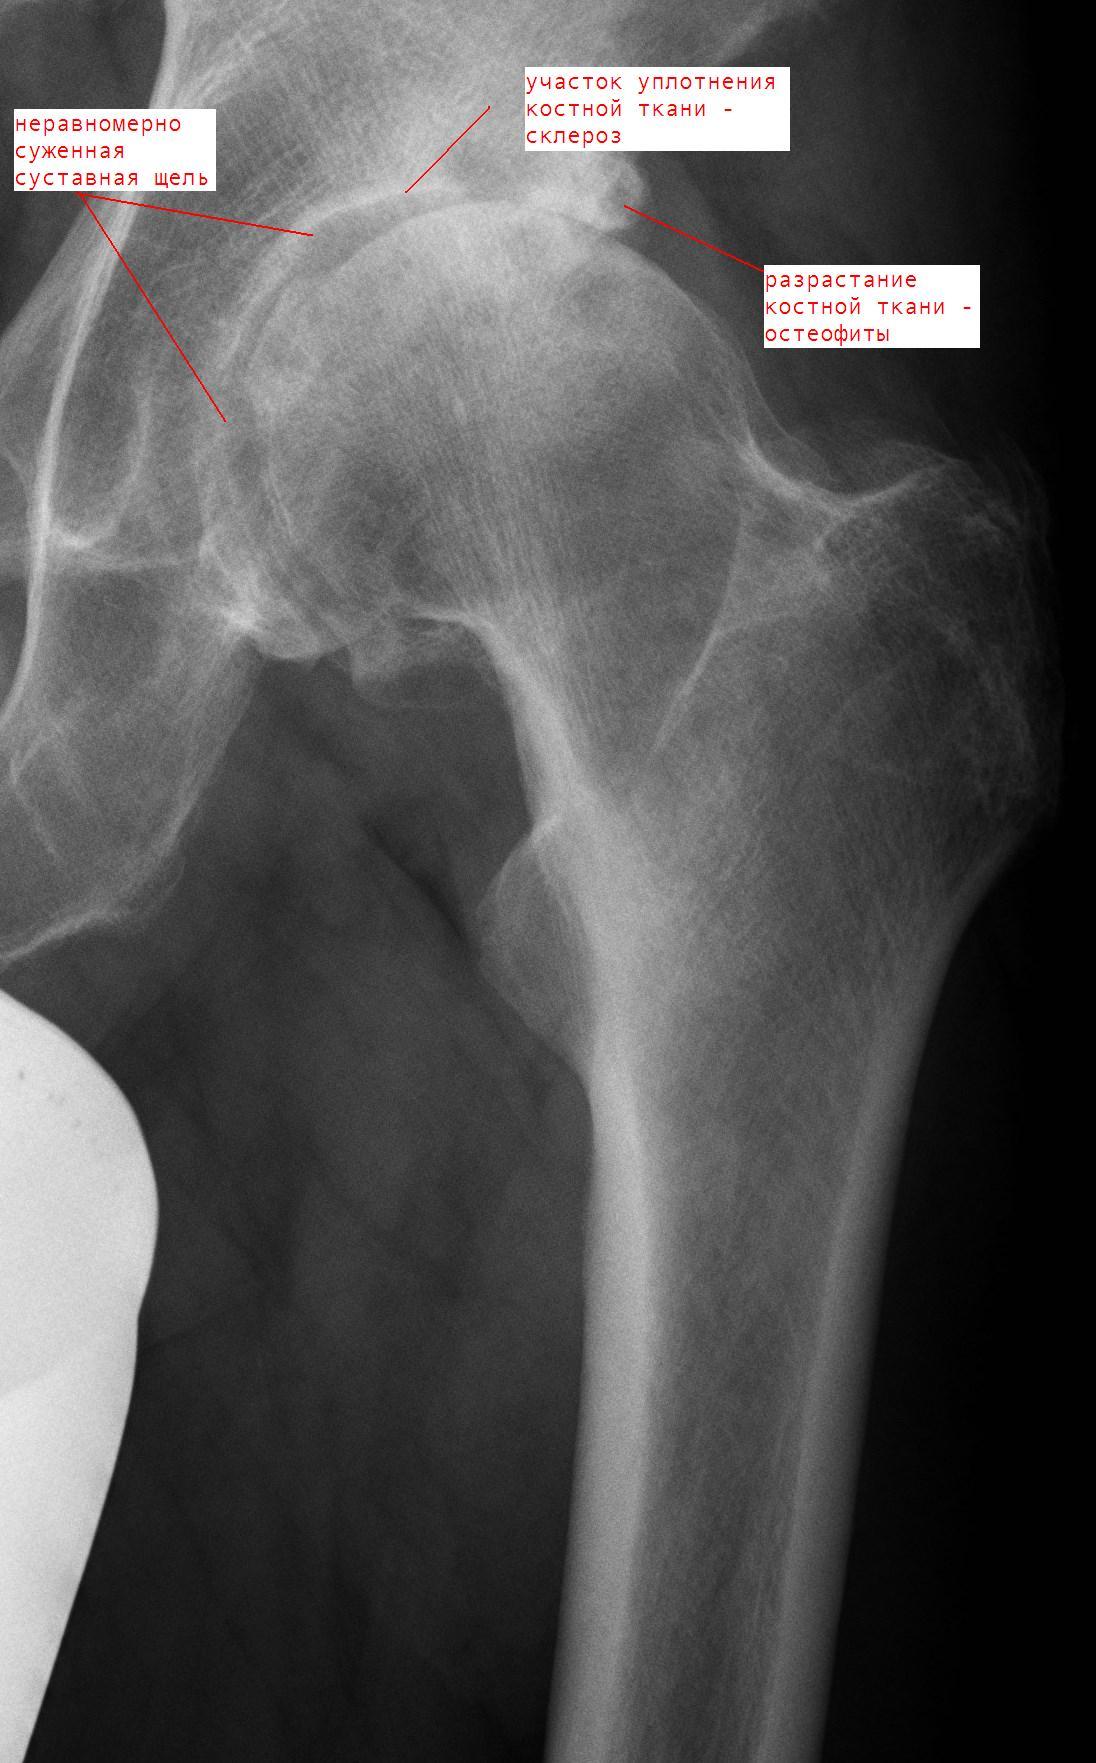

Рентгеновские снимки: Синовит тазобедренного сустава